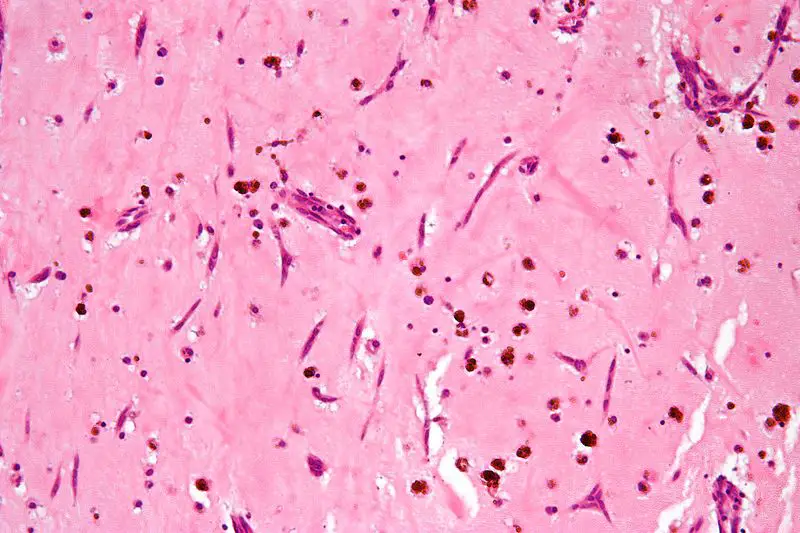

Myxomas typically have a histologic appearance showing an abundance of ground substance and a gelatinous appearance.